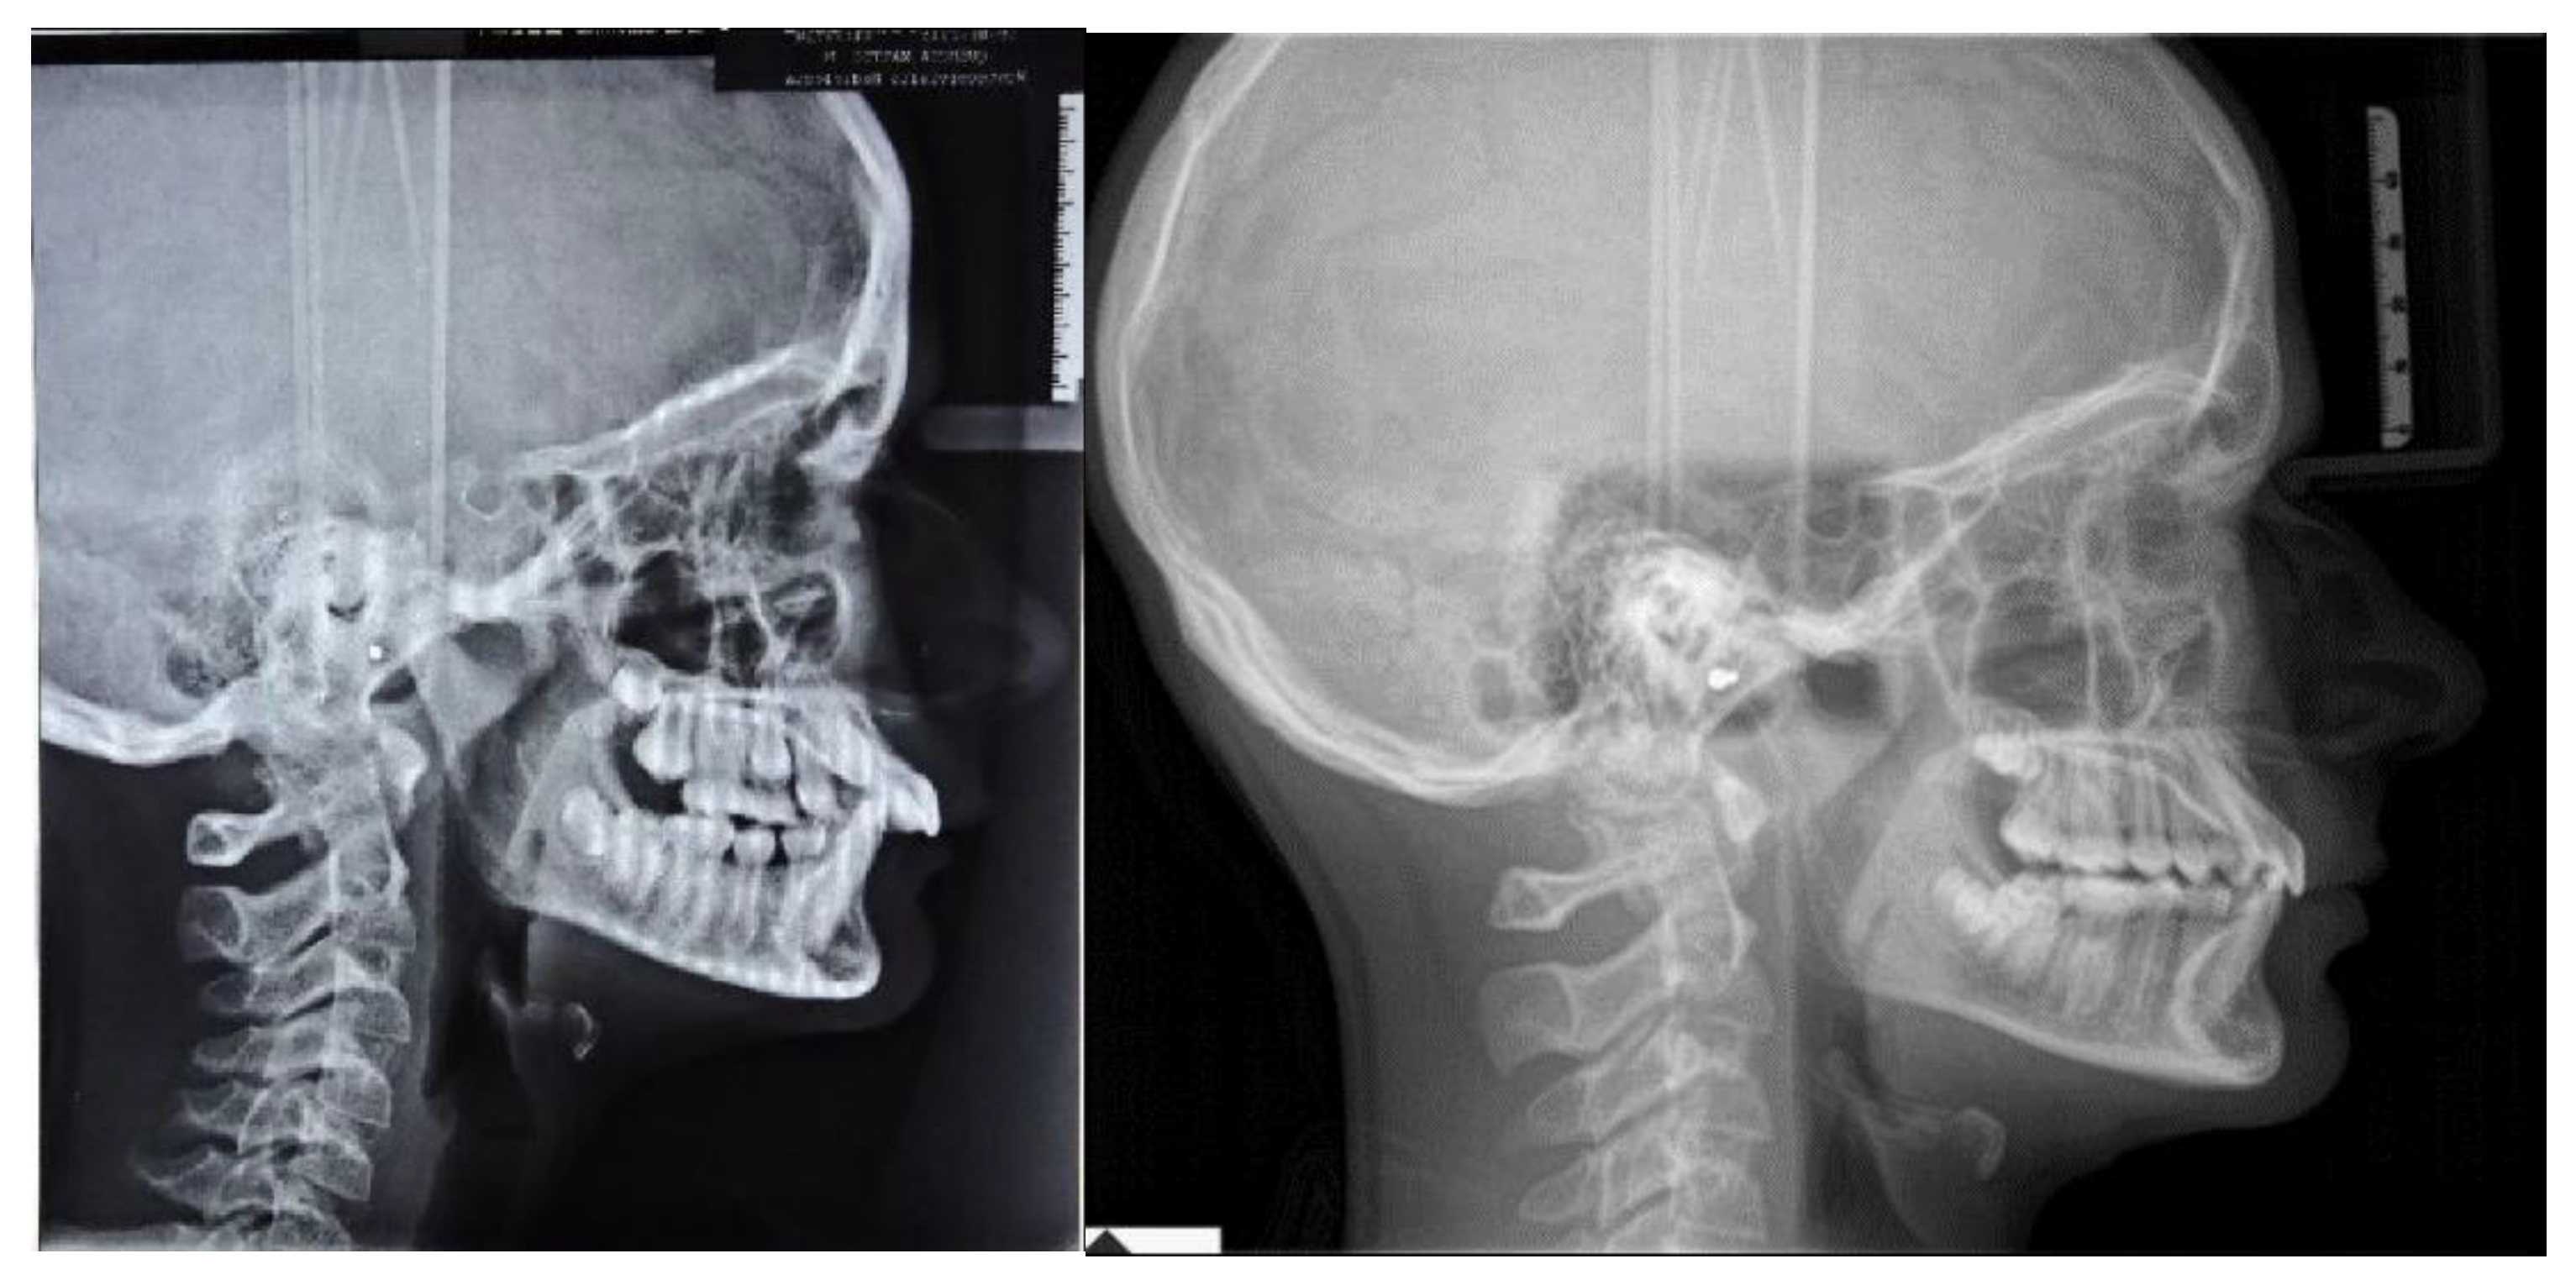

At clinical examination, dental Class I and crowding correction, with proper incisor inclination, and ideal overjet and overbite were achieved (Figure 4).

Figure 4.

Post-treatment intraoral, extraoral photographs and radiographic examination.

Follow-up orthopantomography showed good root parallelism, without any sign of crestal bone loss and apical root resorption; however, a supernumerary maxillary right tooth was noticed (Figure 4).

Post-treatment lateral teleradiograph showed skeletal, dental and aesthetic improvements (Table 1 and Figure 4)

- Skeletal outcomes: cephalometric analysis according to Bjork showed a skeletal Class I relationship (ANB = 2°, Wits = 3 mm). Referring to the anterior cranial base (SN plane: Sella-Nasion), the patient presented a properly sagittal (SNB = 81°) and vertical position of the mandible with an increase in the angle (FMA) between the mandibular plane (ML) and Frankfort’s plane (FH) at the end of treatment (FMA = 21°)

- Dental outcomes: the cephalometric analysis according to Down revealed a change in the inclination of the occlusal plane referring to Frankfort’s plane (OP-FH = 5°), whereas the angle between the maxilla (palatal plane, ANS/PNS) and the Frankfort’s plane was unchanged at the end of treatment (ANS/PNS-FH = 4°). The inclination of the upper incisors was reduced at the end of treatment (Sup/SN = 112°) along with a flat curve of Spee and proper overjet (OJ = 5 mm) and overbite (OB = 4 mm). The inclination of the mandibular incisors remained the same at the end of treatment (IMPA = 90°).

- Aesthetic outcomes: the soft tissue changes involved a straight profile with the jaws proportionately positioned in the sagittal plane. On a frontal view the patient showed an increase in anterior vertical dimension along with an ideal smile arc. From a functional point of view, the lip interposition between the upper and mandibular incisors was corrected (Figure 4 and Figure 5).

Post-treatment lateral teleradiograph showed a significant improvement in the sagittal bone relationship (Table 1), along with good vertical control, and a correct inclination of the upper and mandibular incisors. (Figure 4). A good proportion between the upper and mandibular arch width and shape was achieved along with a flat curve of Spee. Functional and aesthetic outcomes were stable at one-year follow-up and four-year follow-up (Figure 4, Figure 5 and Figure 6).